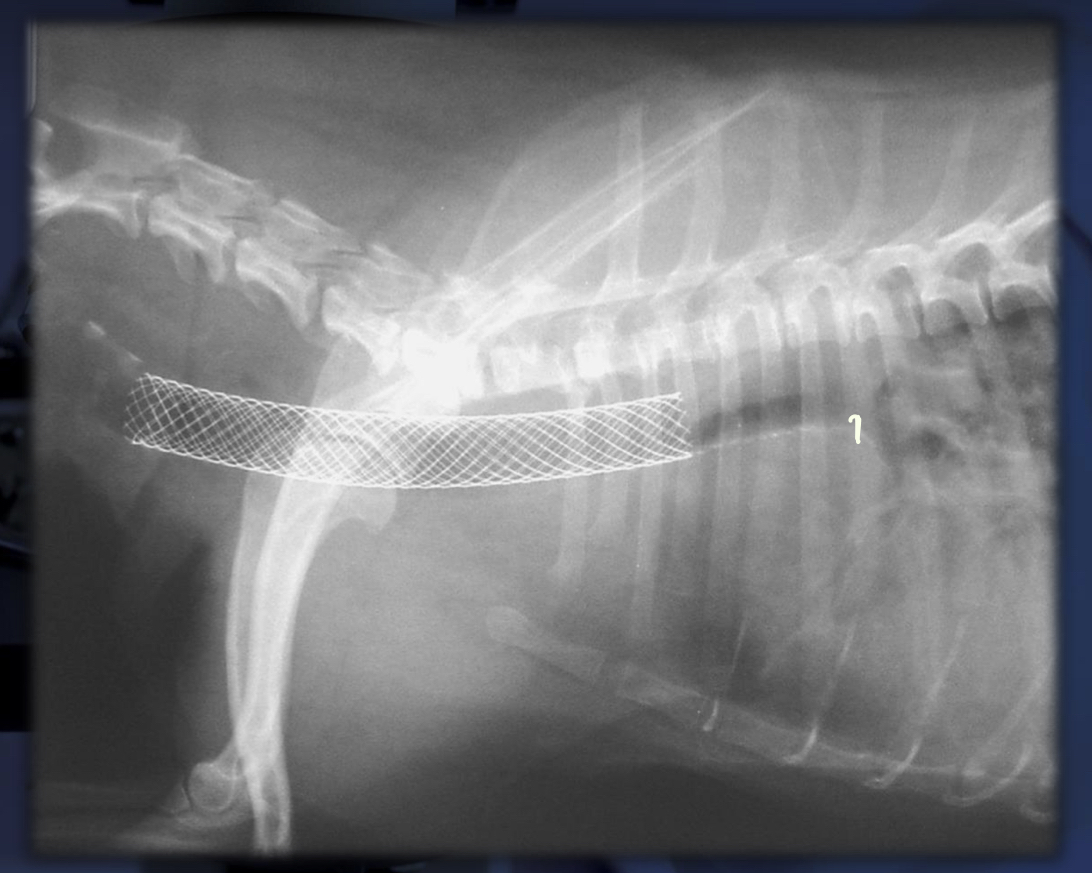

How far down are intraluminal stents placed for the repair of a collapsed trachea? How does this technique compare to extraluminal stents?

A

1 cm in front of bifurcation to the end of the larynx

• clinical improvement in > 90%

• minor complications

• 5% mortality rate

What are 3 types of intraluminal stents? What are the 2 characteristics of a proper stent?

1. nitinol mesh

2. stainless steel mesh

3. braided nitinol stents

inert and can take a beating from the heart

What are the 3 major advantages to the use of intraluminal stents over extraluminal?

1. minimally invasive placement 2. decreased anesthesia time 3. access to the entire cervical and thoracic trachea

How are intraluminal stents measures?

- a probe with centimeter markers are slipped down the esophagus - a measurement is taken based on these markers from the larynx at the back of C2 to the tracheal bifurcation for the length - compare the collapsed diameter to the optimal diameter of the trachea, aiming to increase the collapsed segment by 20%

How can the correct placement of an intraluminal stent be confirmed?

- post-op radiographs: ensures its actually in trachea, makes sure it runs from the back od C2 to the tracheal bifurcation - fluoroscopy: can ensure the dynamic stability of the stent - tracheostomy: direct visualization to confirm 360 degree contact to avoid trapped infection